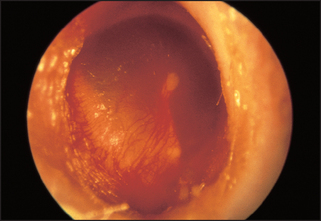

Inspect the tympanic membrane (ear drum) by introducing the speculum further into the canal in a forward but downward direction. The normal tympanic membrane is a pearly grey colour. It is ovoid in shape and semi-transparent (see Figure 38.15). The upper fifth is called the pars flaccida and the lower four-fifths are called the pars tensa. The handle of the malleus is often visible near the centre of the pars tensa. From the lower end of the handle a bright cone of light should be visible: the light reflex. The presence or absence of the light reflex is not a sensitive or a specific sign of disease (see Figures 38.16 and 38.17). Note the colour, transparency and any evidence of dilated blood vessels (hyperaemia—a sign of otitis media; see Figure 38.17). Look for bulging or retraction of the tympanic membrane. Bulging can suggest underlying fluid or pus in the middle ear. Retraction means a reduction in pressure in the middle ear and is a sign of a blocked Eustachian tube. Perforation of the tympanic membrane should be noted (see Figure 38.18).

Figure 38.15 The tympanic membrane as viewed through an otoscope (From Mir MA. Atlas of clinical diagnosis, 2nd edn. Edinburgh: Saunders, 2003, with permission.)

Figure 38.16 The detail of the tympanic membrane (From Mir MA. Atlas of clinical diagnosis, 2nd edn. Edinburgh: Saunders, 2003, with permission.)

Figure 38.17 Otitis media with hyperaemia of the tympanic membrane (From Mir MA. Atlas of clinical diagnosis, 2nd edn. Edinburgh: Saunders, 2003, with permission.)